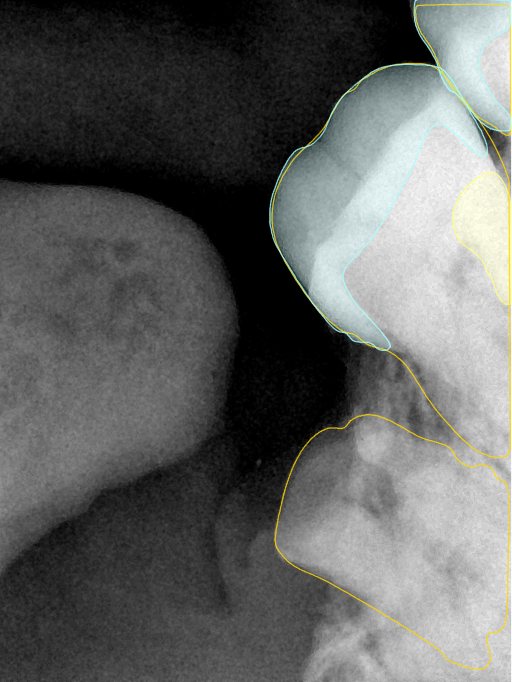

CR/DR 牙齿分割阶段记录

当前进展

- 完成了 CR/DR 牙齿相关分割训练

- 当前结果已经达到阶段预期,但仍有细节问题需要继续处理

相关测试

遇到的问题

- 训练过程中出现过 mask 下移问题

- 部分结果会出现 box 填充异常

- mask 边缘仍然有比较明显的锯齿感

参考

第二版算法问题测试